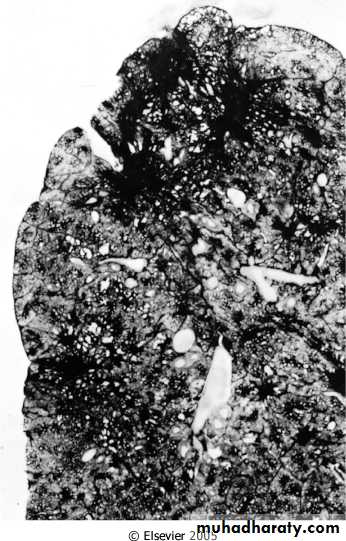

Simplest forms of pneumoconiosis , usually universal , harmless , rarely it may progress to progressive massive fibrosis.Silicosis :

May be encountered in sandblasting, mining, stone cutting, tunneling, ceramics…..

It induces progressive inflammation lead to the formation of fibrotic masses .

It may associated with increased susceptibility to T.B & lung cancer.Morphology

-Gross, fibrotic nodules and scars in the upper zones of the lungs.Fibrotic lesions may also occur in the hilar lymph nodes and pleura.

-Microscope, concentric layers of hyalinized collagen.

Collagenous silicotic nodule